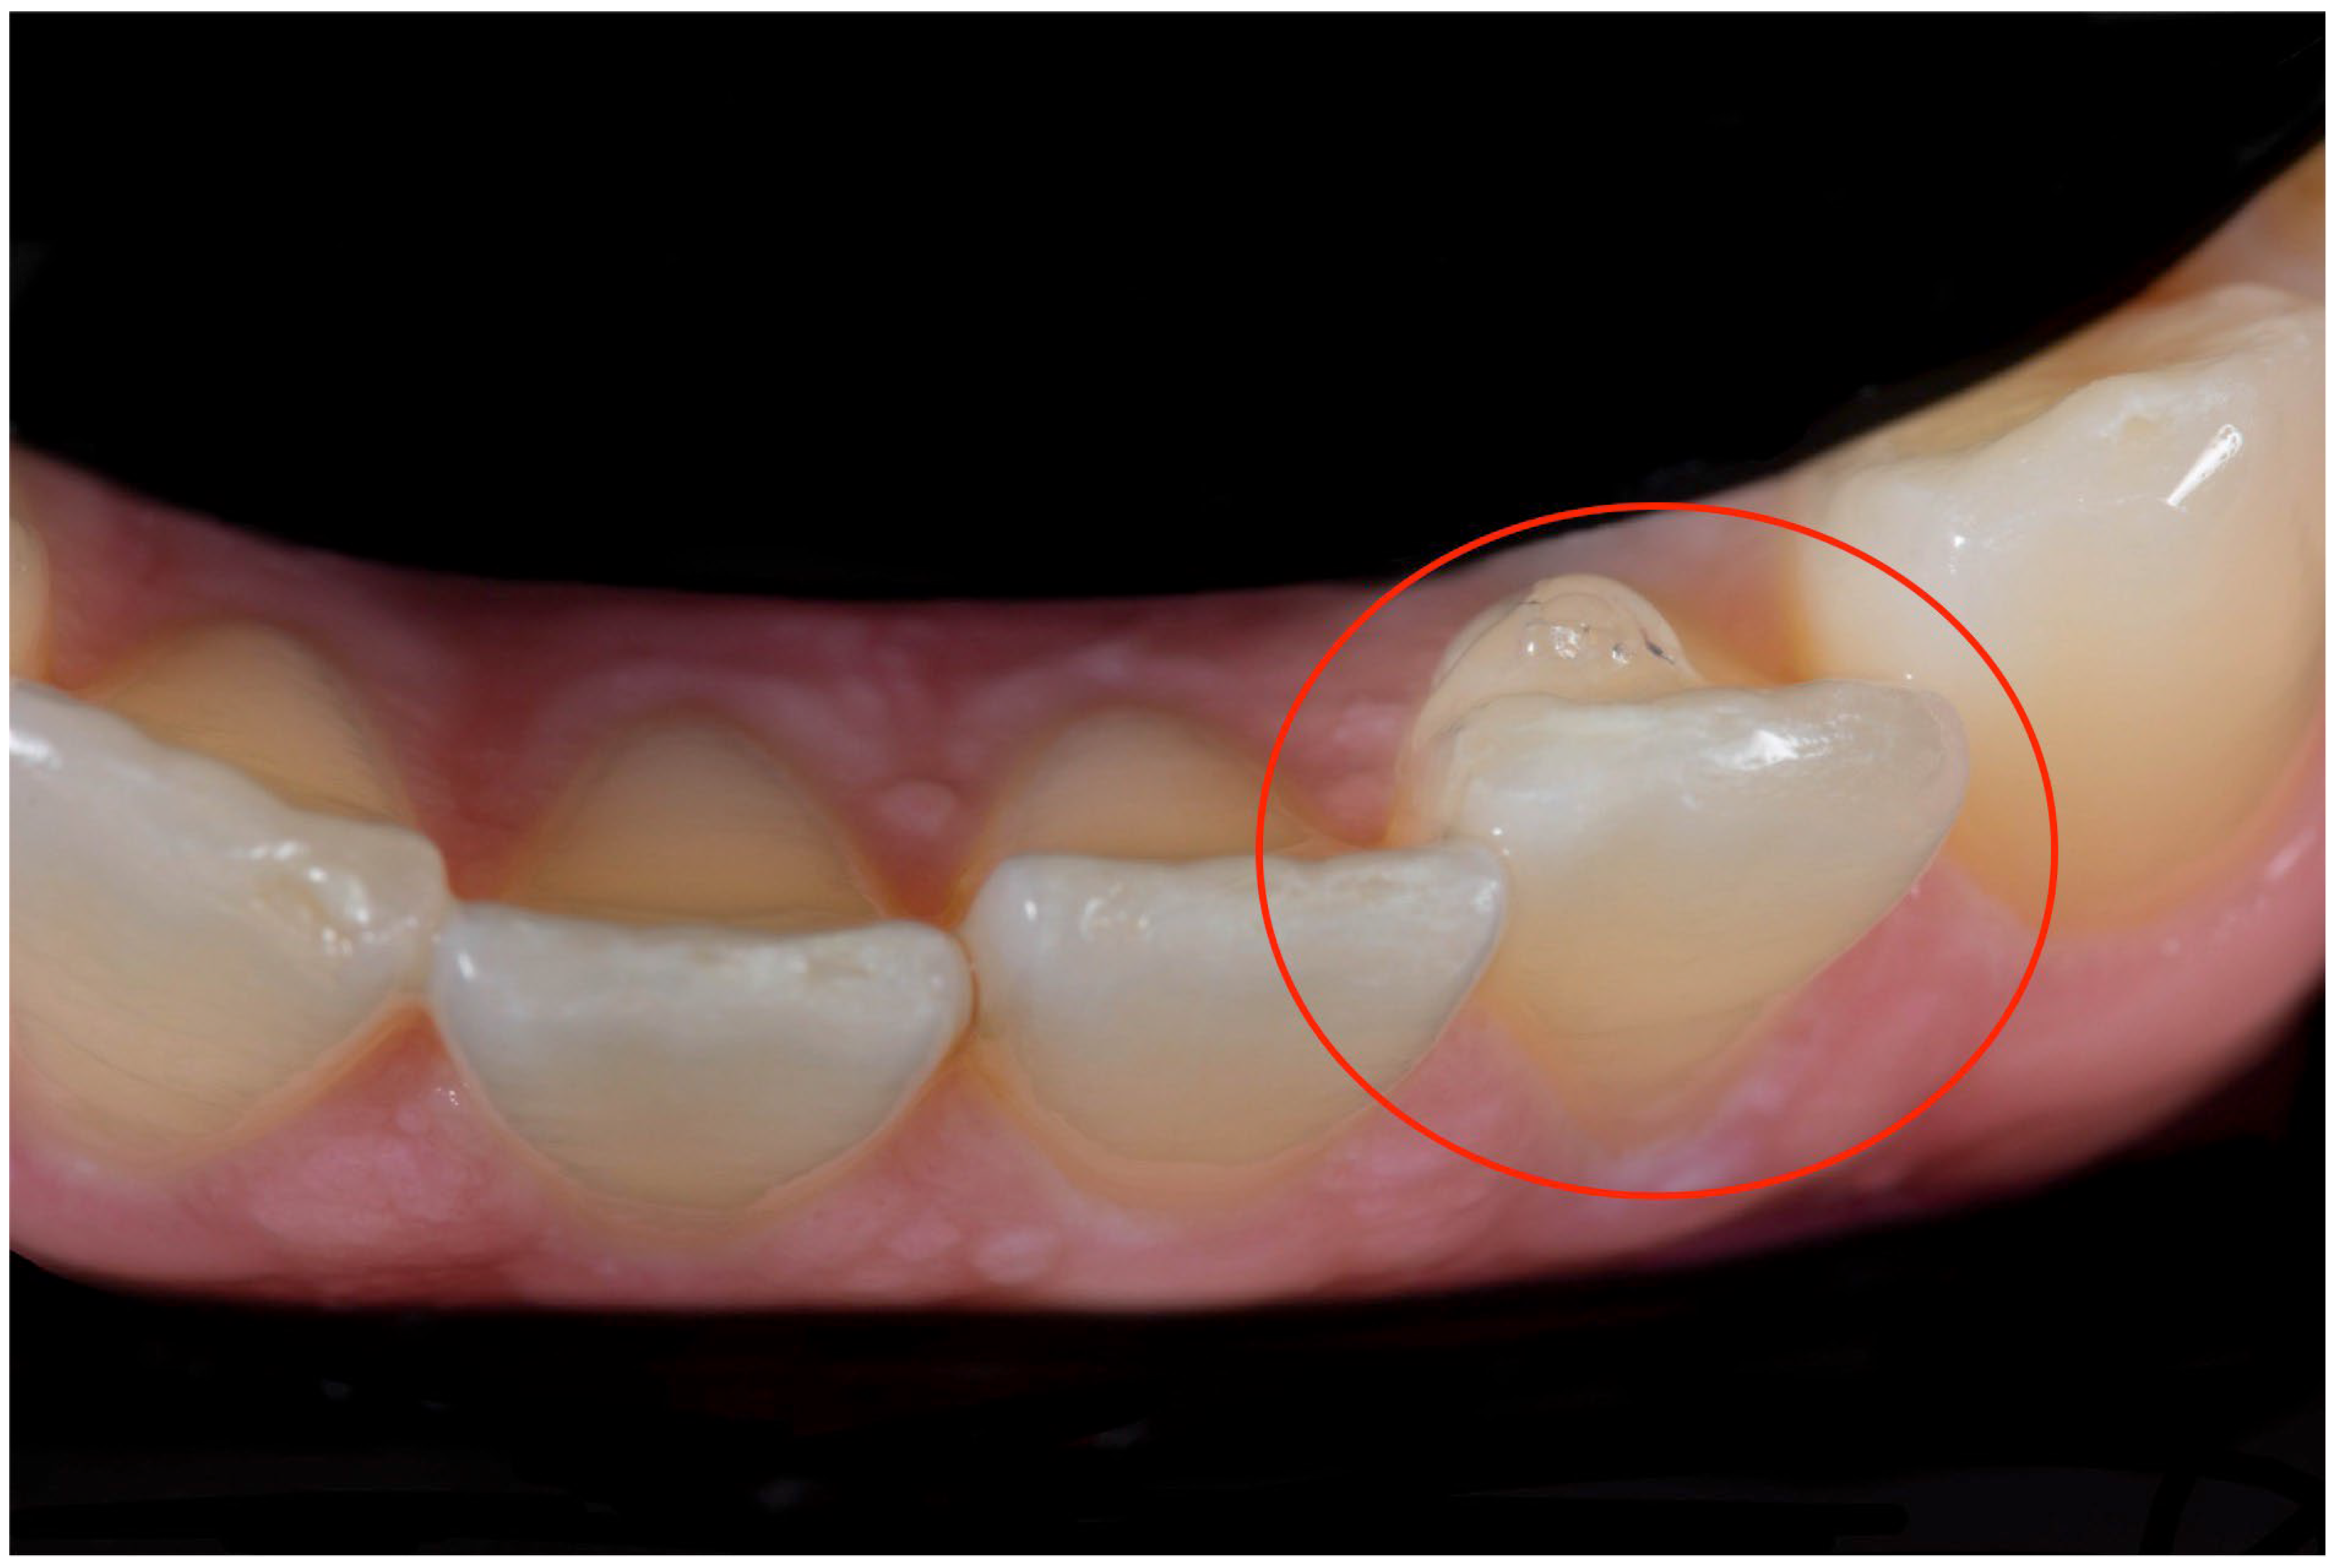

Orthodontic therapy with clear aligners has expanded rapidly in recent years to meet the growing demand for a comfortable, aesthetic treatment [1,2,3]. Clear aligners generally consist of a series of transparent polymer trays that fit closely over the teeth. These aligners are intended for continuous use by the patient, except during meals and oral hygiene routines, and are typically replaced every one to two weeks to facilitate planned orthodontic tooth movements. With the increased use of the devices, there has been a considerable evolution in the underlying technologies, leading to improved results and expanding the range of application of the treatment [4,5]. Clear aligner therapy does not rely exclusively on the use of aligners: more complex cases can be dealt with using aids such as resin attachments, divots, anchors, precision cuts, bite ramps, and power ridges [6,7]. To remove the potential need for correction where there are discrepancies between the planned and actual tooth movements, or, in any case, to improve the efficiency of the biomechanical system, it has been suggested that a layer of elastic resinous material be applied to the surface of the tooth or teeth to be repositioned (Figure 1). For example, a hill could be placed on the lingual side to generate a buccal movement of the tooth.

Figure 1.

Clinical picture of the “Hill” (red circle).